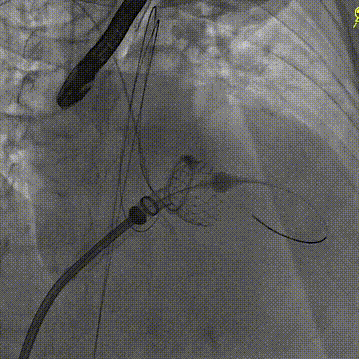

随后在超声引导下进行房间隔穿刺,最终穿刺高度约3.4cm,顺利建立经房间隔入路。而后沿成环导丝于二尖瓣环下植入固定环,通过DSA及3D超声确认固定环完全关闭且位置合适。沿股静脉送入HighLife TSMVR瓣膜,首先释放瓣膜心室端,随后牵拉输送器,超声下观察,使瓣膜心室端与固定环充分贴合,旋即保持拉力并释放瓣膜心房端,人工瓣膜脱钩,在固定环的辅助下,于二尖瓣瓣环平面完成自同轴,最后逐步撤出人工瓣膜输送系统和固定环输送系统。即刻超声评估提示二尖瓣返流完全消失,无瓣周漏,人工瓣膜植入位置理想,形态良好,跨瓣压差1mmHg;LVOT压差6mmHg,无左室流出道梗阻风险;房间隔4mm左向右分流,无即刻封堵指征。手术成功完成!

瓣膜释放心室端

瓣膜释放心房端